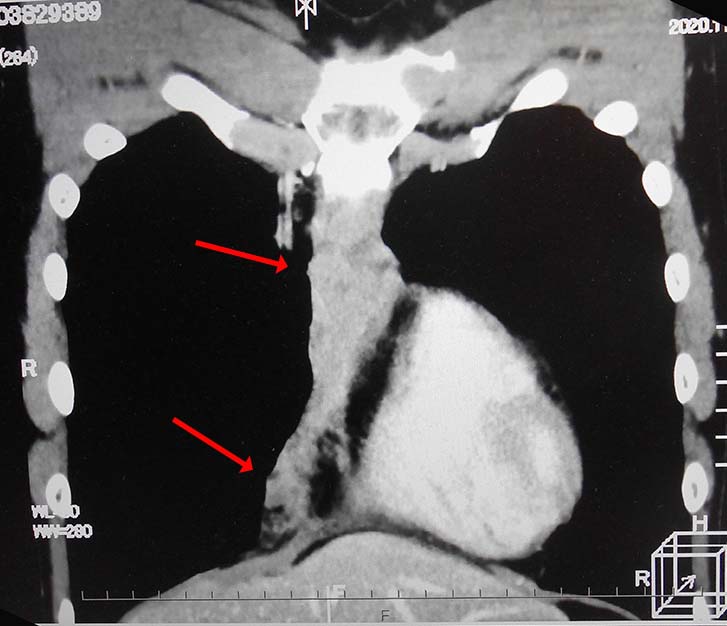

前縦隔や右心横隔膜角部に不定形, 不均一でべたっとした腫瘤状軟部濃度域を認める. 節外浸潤を伴ったリンパ節転移の可能性を考える.

画像: 左精巣腫瘤. 縦隔リンパ節転移疑い.